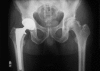

Background: Offset in THA correlates to abductor muscle function, wear, and impingement. Femoral offset after THA is not independent of the cup center of rotation (COR) so hip offset, a combination of femoral offset and change in hip COR, becomes the important measurement.

Questions/purposes: We therefore asked whether hip offset in arthritic hips would correlate with cup COR; whether offset could always be balanced within 6 mm of contralateral normal hips; and whether hip length could also be kept within 6 mm.

Methods: We compared hip offset of arthritic and contralateral normal hips on radiographs in 82 patients (82 hips) who had THA. We used computer navigation in all patients with the aim of reconstructing the hip offset and to compare hip offset change to the quantitative change of the hip COR.

Results: The preoperative radiographic change to equalize the offset ranged from -12 to +21 mm (mean, 1.5); postoperatively the change was 1.4 ± 6.4 mm and was within ± 6 mm in 78 of 82 hips. As COR displaced superiorly from 3 to 6+ mm the offset had to be substantially increased. Only with COR 0-3 mm superior and 0-5 mm medial was offset always within 5 mm.

Conclusions: Hip offset reconstruction was directly related to the position of the hip COR, and navigation allowed quantitative control of offset and hip length.